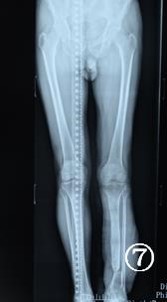

患者 男,68岁。因左小腿外伤后骨外露伴皮肤缺损20天入院。左小腿外支架固定中,左胫骨大段骨质外露,左小腿大面积皮肤软组织缺。入院后行清创死骨去除VSD术。术后1周行左胫骨骨迁移+左背阔肌游离移植术+取皮植皮术(图1-5)。术后14天开始胫骨骨迁移,创面一期愈合。术后1年随访,皮瓣外形良好(图6)。术后20月,迁移骨成骨良好,骨端愈合,拆除外固定支架(7)。